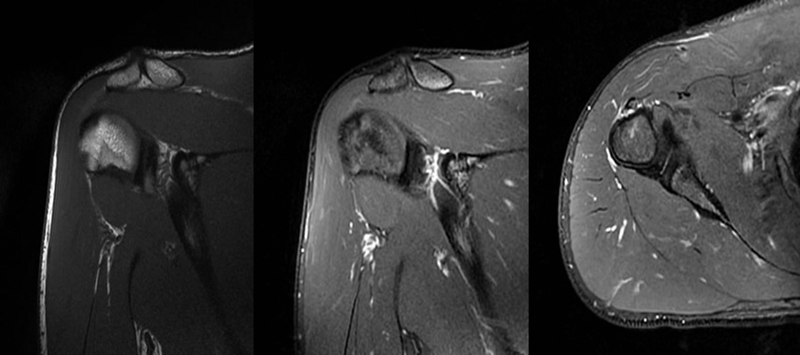

2、MRI检查

MRI目前是诊断肩袖疾病中最常用的检查,可以直观的观察肩袖肌腱。

图24 a.肩袖全层撕裂;b.正常MRI

图25 巨大肩袖损伤(冈上肌)